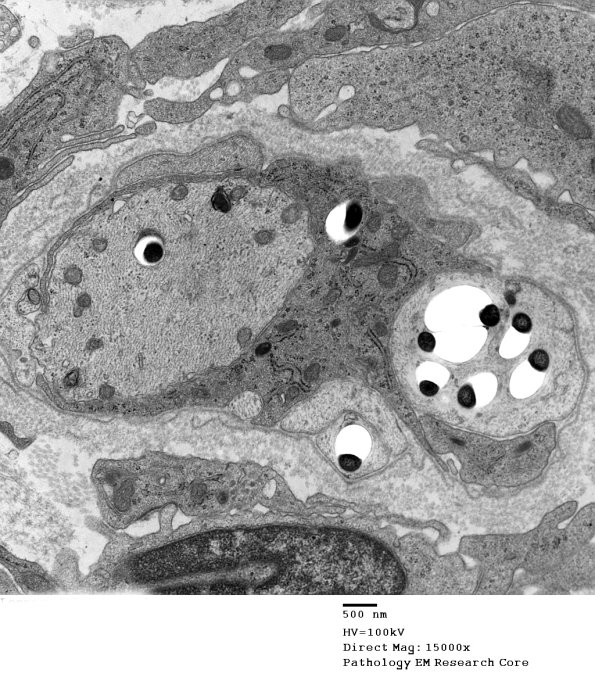

In this case the Schwann cell contains organisms adjacent to and within the demyelinated axon. (electron micrograph)